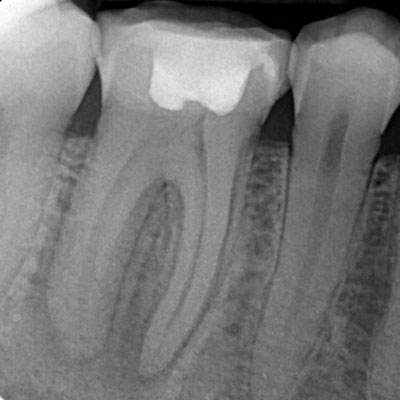

O exame radiográfico periapical proporciona ao dentista a visualização do dente em toda sua extensão, desde a coroa ao ápice, o espaço periodontal e o tecido ósseo.

A radiografia periapical ou RX periapical é um exame utilizado para mostrar radiograficamente a anatomia de um ou mais dentes (desde a coroa ao final da raiz), assim como as estruturas anatômicas vizinhas, ou seja, que estão ao redor dos dentes.

Esta radiografia pode ser usada para estudar qualquer dente (molar, pré-molar, e incisive os caninos) seja na arcada dentária superior ou na inferior para fins de diagnóstico e tratamento.